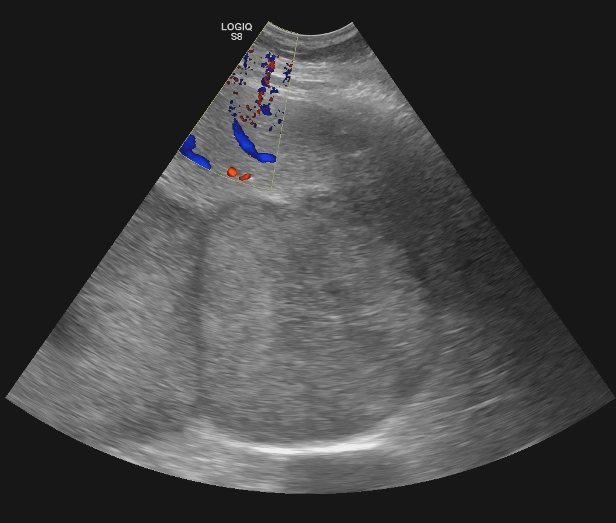

Se realiza ecografía abdominal en la consulta que muestra abundantes lesiones ocupantes de espacio en ambos lóbulos hepáticos, alguna de gran tamaño.Otras pruebas complementarias realizadas (si existen)

Hígado con múltiples metástasis y ambos lóbulos, la más gruesa de uns 10,2 cm en los segmentos VI y VII. Colecistolitiasis. Vía biliar no dilatada.Esplenomegalia con nódulos 12 y 14 mm inespecíficos. Nódulos suprarrenal izquierdo de 46 mm y dos derechos de 14 y 18 mm, inespecificos. Páncreas de medida y morfología normal. No hay signos de uropatía obstructiva. Riñones dentro de la normalidad con el nefrograma simétrico. Adenopatías retroperitoneales de predominio retrocavales y enteraortocava, la mas gruesa de 19 mm. Lesiones líticas en las costillas, esternón, vertrebrales y pelvianas. Conclusión: Enfemerdad neoplasia con diseminacion pulmonar y hepática, osea, ganglionar y probablemente esplenica y suprarrenal bilateral. No se identifica origen.

Biopsia de nódulo hepático positiva para melanoma maligno.